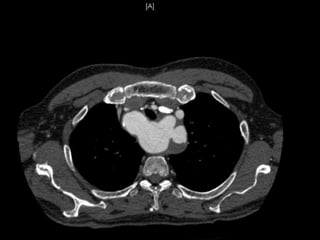

Cas 1

 CTA Pre-opératoire:

 Artere sous clavière aberrante droite

○ Origine a partir de l’aorte thoracique descendante,

distal a l’artere sous-clavier gauche

○ Trajet derriere l’œsophage et la trachée

 Diverticule de Kommerell a l’origine de l’artere

sous-claviere aberrante droite (diamètre 4.6 cm)

 Origine commune des artères carotidiennes

(CCA)

 Artere vertébrale droite dominante qui origine de l

artere sous-clavier aberrante droite

 Aucuns autres anévrismes ou sténoses